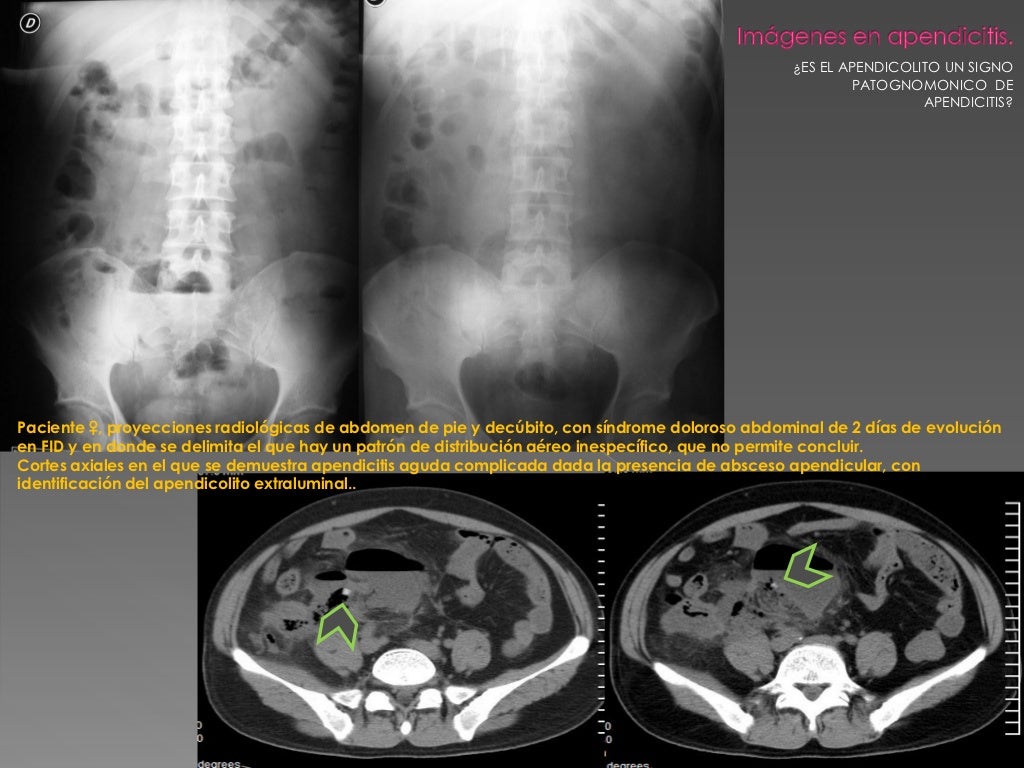

Es el apendicolito un signo patognomonico de apendicitis